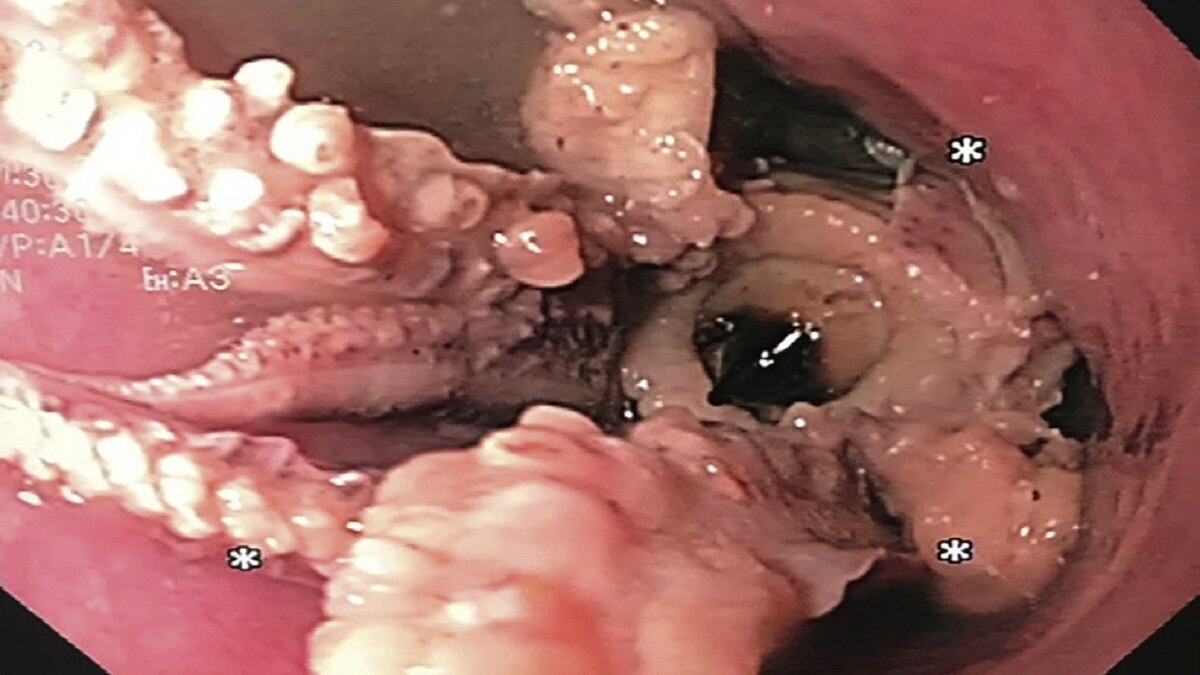

डॉक्टर यह देखकर हैरान रह गए कि एक शख्स के फूड पाइप में एक ऑक्टोपस फंसा हुआ है. आपने बिल्कुल रही पढ़ा- ये छह या आठ पैरों वाला ऑक्टोपस ही था. बाद में एसोफैगोगैस्ट्रोडोडेनोस्कोपी - एक छोटी, लचीली ट्यूब से जुड़ी एक गैस्ट्रोइंटेस्टाइनल जांच के दौरान एक ऑक्टोपस को एसोफैगस-पेट की सीमा से दो इंच की दूरी पर फंसा हुआ पाया गया.

अमेरिकन गैस्ट्रोएंटेरोलॉजिकल एसोसिएशन (एजीए) ने बताया कि ऑक्टोपस को बाहर निकालने के शुरुआती प्रयास असफल रहे. इसके बाद डॉक्टरों ने सावधानीपूर्वक एंडोस्कोप को ऑक्टोपस के पीछे से पेट में डाला और रेट्रोफ्लेक्स किया. ऑक्टोपस के सिर को पकड़ने और उसे हटाने के लिए फोरसेप का उपयोग किया गया. इस प्रक्रिया के दो दिन बाद मरीज को पूरी तरह से ठीक होने पर छुट्टी दे दी गई.